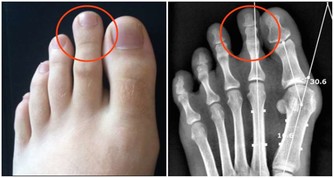

排便時3個異常,警惕是身體在“報警”

1. 出現血便

血便是消化道出血的一種表現,當然,需要排除食物的因素(如吃了豬血、豬肝、首烏、地黃等)。

由於出血部位、出血量,以及血液在消化道停留時間的不同,便血可呈鮮紅、暗紅、柏油樣色,或者是隱血便。

鮮血或暗紅血便

直腸、肛門、結腸等距離肛門較近部位的出血,如痔瘡、腸息肉、直腸脫垂、肛裂等導致的出血。